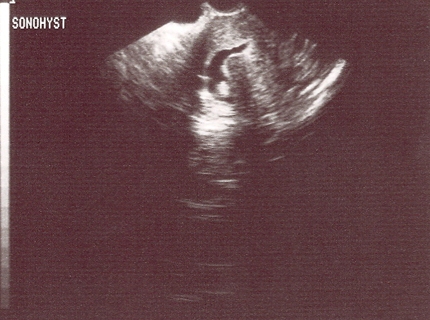

Sonohysterography demonstrates a posterior submucous uterine fibroid deforming the posterior endometrial cavity

From the personal collection of Dr M.F. Mitwally and Dr R.J. Fischer; used with permission